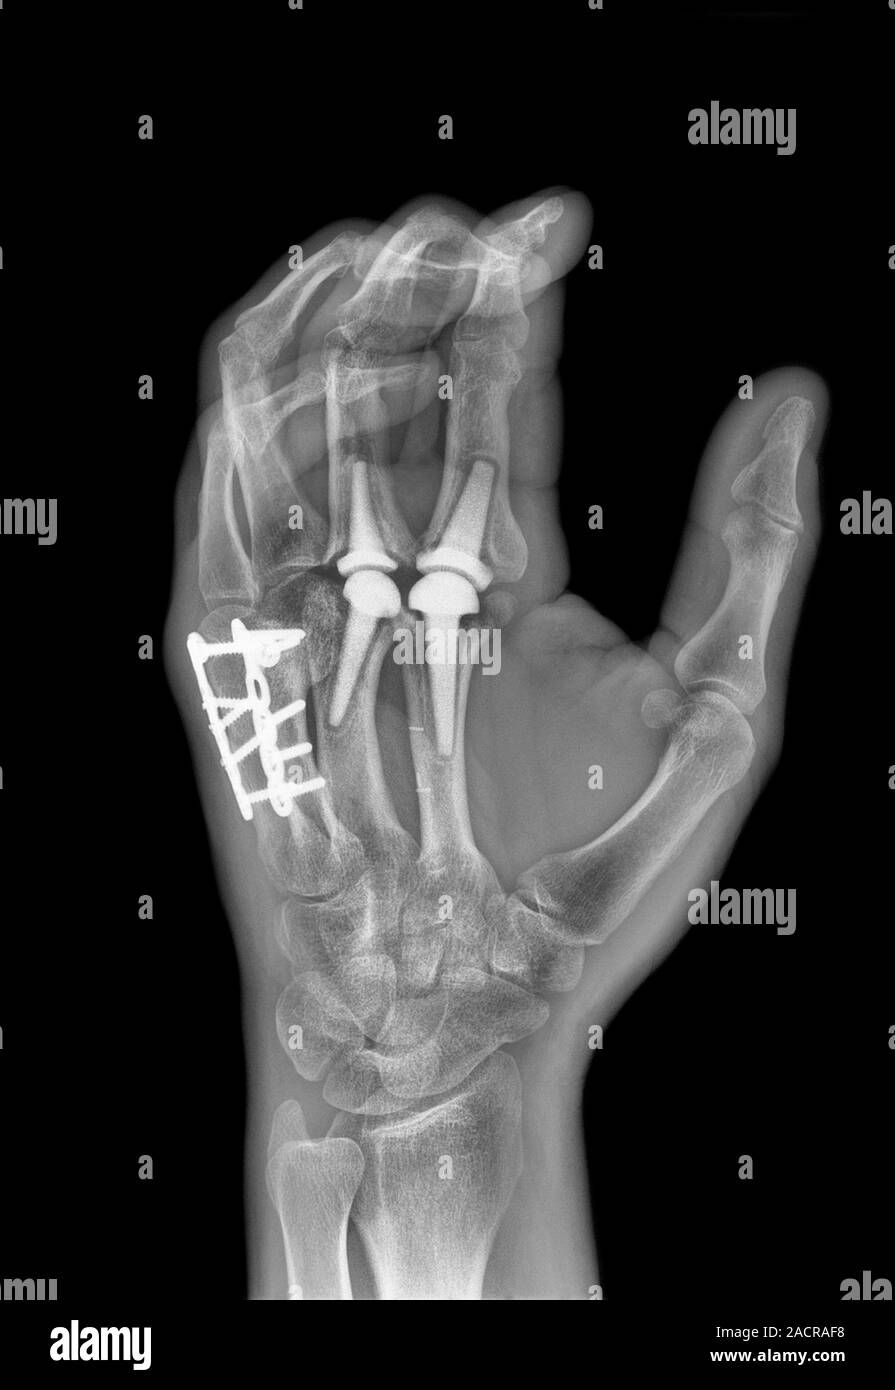

From www.alamy.com

Knuckle replacement. Xray of the hand of a 41 year old male patient Can Knuckle Joints Be Replaced Learn about the two main surgical options for hand arthritis: Learn about the surgical procedure to replace the arthritic knuckle joints of your hand with silicone implants or spacers. An mcp joint replacement is most commonly performed when your knuckle joint is painful, stiff or cannot move because of arthritis or injury. Arthritis can affect the knuckles of your fingers. Can Knuckle Joints Be Replaced.

From www.sciencephoto.com

Knuckle joint replacement surgery Stock Image C011/0789 Science Can Knuckle Joints Be Replaced Finger joint replacements are most frequently performed to treat arthritis; Find out how implants can reduce pain, restore motion and improve function in the hand. However they may also be used after an injury to the joint. An mcp joint replacement is most commonly performed when your knuckle joint is painful, stiff or cannot move because of arthritis or injury.. Can Knuckle Joints Be Replaced.